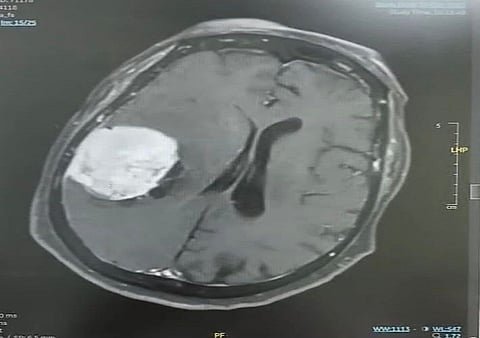

وأوضح تجمع المدينة المنورة الصحي أن المستفيدة راجعت المستشفى وهي تعاني من الأعراض المذكورة، وبعد إجراء الفحوصات السريرية وصور الرنين المغناطيسي تبيّن وجود ورم كبير في الجهة الجدارية اليمنى من الدماغ، وبعد التنسيق مع الأقسام ذات العلاقة واستكمال التحضيرات الطبية، أُدخلت المريضة إلى غرفة العمليات حيث نجح الفريق الطبي – بفضل الله – في استئصال الورم بالكامل بدقة عالية دون مضاعفات.